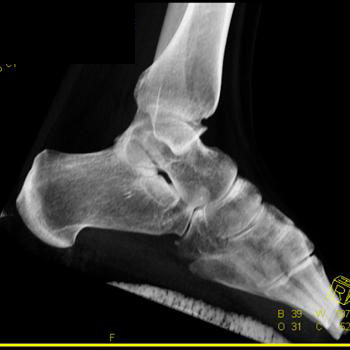

Clinical History: 12 year old female who fell down steps. She presents with left lower extremity pain.

CT Findings: Nondisplaced triplane left ankle fracture involving medial malleolus, with opened epiphysis.

Diagnosis: Minimally displaced of the medial malleolus and widening of the epiphyseal plate defined.

Outcome: Nonweightbearing. She was placed in a splint.